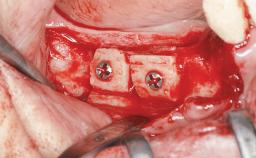

Shell Technique for Horizontal and Vertical Maxillary Bone Augmentation in a Partially Edentulous Patient with Aggressive Periodontal Disease

A 46-year-old woman was referred for treatment whose main complaints were mobility of her fixed partial dentures (right maxilla and left mandible) and periodontal bleeding during function. She also reported having taken systemic antibiotics to treat recurrent swelling in the area of the upper left molars. The patient had not seen a dentist for at least 2 years. She did not smoke and had no history of major systemic disease other than two minor orthopedic procedures some years back. The first-visit examination revealed poor plaque control, tooth mobility, periodontal disease, and a residual dentition widely associated with deep periodontal pockets.